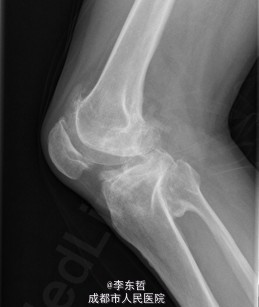

初步诊断:1、左侧股骨头坏死伴内收肌挛缩(Ficat IV期);2、右侧股骨头坏死(Ficat IV期);3、右膝骨关节炎伴外翻畸形;入院后积极完善术前检查及准备,择期行手术治疗。